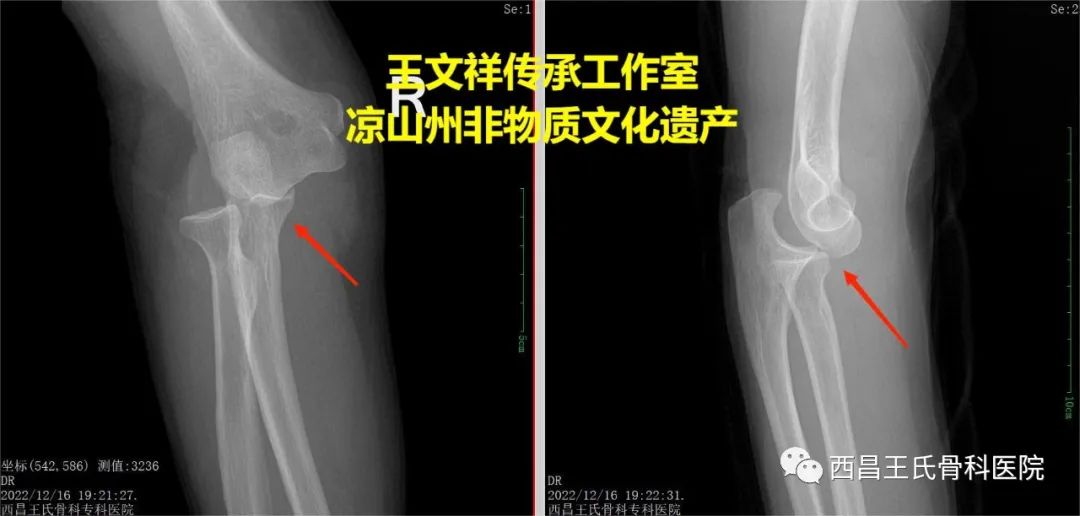

手法复位病例五:82岁、肘关节脱位

图片

复位前

复位后